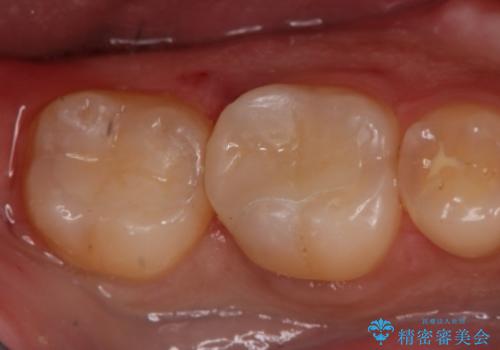

切削量・形態を考慮し、セラミックインレーでの治療を計画しました。

虫歯が深い場合、痛みなどの症状が出る可能性がありますが、経過は良好でご本人も満足されています。